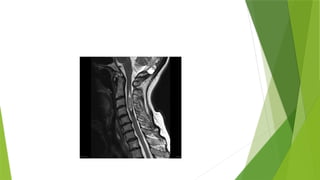

 Multiple variable sized cervicomedullary and upper cervical cord shows intra

medullary enhancing lesions having average size of 8 x4 mm suggestive of

ependymoma.

 Multiple variablesized extra axial broad base lesion are noted in bilateral Para falx region, frontal and parietal lobes with average size of 1.3 x 1 cm.  Two other altered signal intensity lesion arising from 7th and 8th nerve are noted in left CP angle and protruding into left internal acoustic meatus giving appearance of ICE CREAM CONE. Returning signals are iso intense on T1 and T2 and showing avid enhancement on post contrast images and no restriction on DWI.  Multiple variable sized cervicomedullary and upper cervical cord shows intra medullary enhancing lesions having average size of 8 x4 mm suggestive of ependymoma.